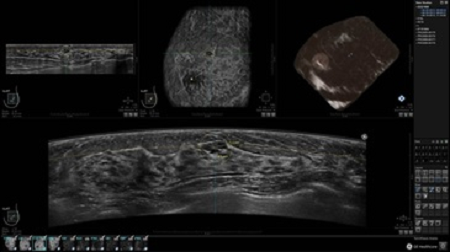

GE INVENIA ABUS – это современный УЗИ аппарат, который создан для точной и эффективной диагностики сканирования с высокой плотностью молочных желез. Выявляемость патологий раковых и предраковых стадий заболевания составляет 55%, что в конечном счете позволяет ставить врачу точные и своевременные диагнозы. Традиционные методы использования маммографии не показывают такой выявляемости, ограничиваясь лишь 3-38%.

УЗИ-аппарат GE INVENIA ABUS позволяет проводить максимально операторонезависимые процедуры, что значительно снижает риск неправильной постановки диагноза и сопутствующие издержки на обработку информации. Система готовит отчет в течение 3-х минут после сканирования, это безусловное преимущество по сравнению с обычным УЗИ сканером.

• датчик с изогнутой апертурой для качественного исследования

• сканирование одной грудной железы в трех проекциях не более 60 сек.;

• обработка результатов за три минуты.

Возможности встроенной УЗ-системы:

• Увеличение или уменьшение степени сжатия грудной железы;

• Функция автоматического сканирования активируется одним нажатием;

• Возможность отмены сканирования;

• Глубина проникновения УЗ-лучей – до 50 мм;

• Одно детализированное изображение можно получить менее чем за 1 минуту

• Многорядная светодиодная подсветка;

• Встроенный сверхширокий вогнутый датчик С15-6ХW.